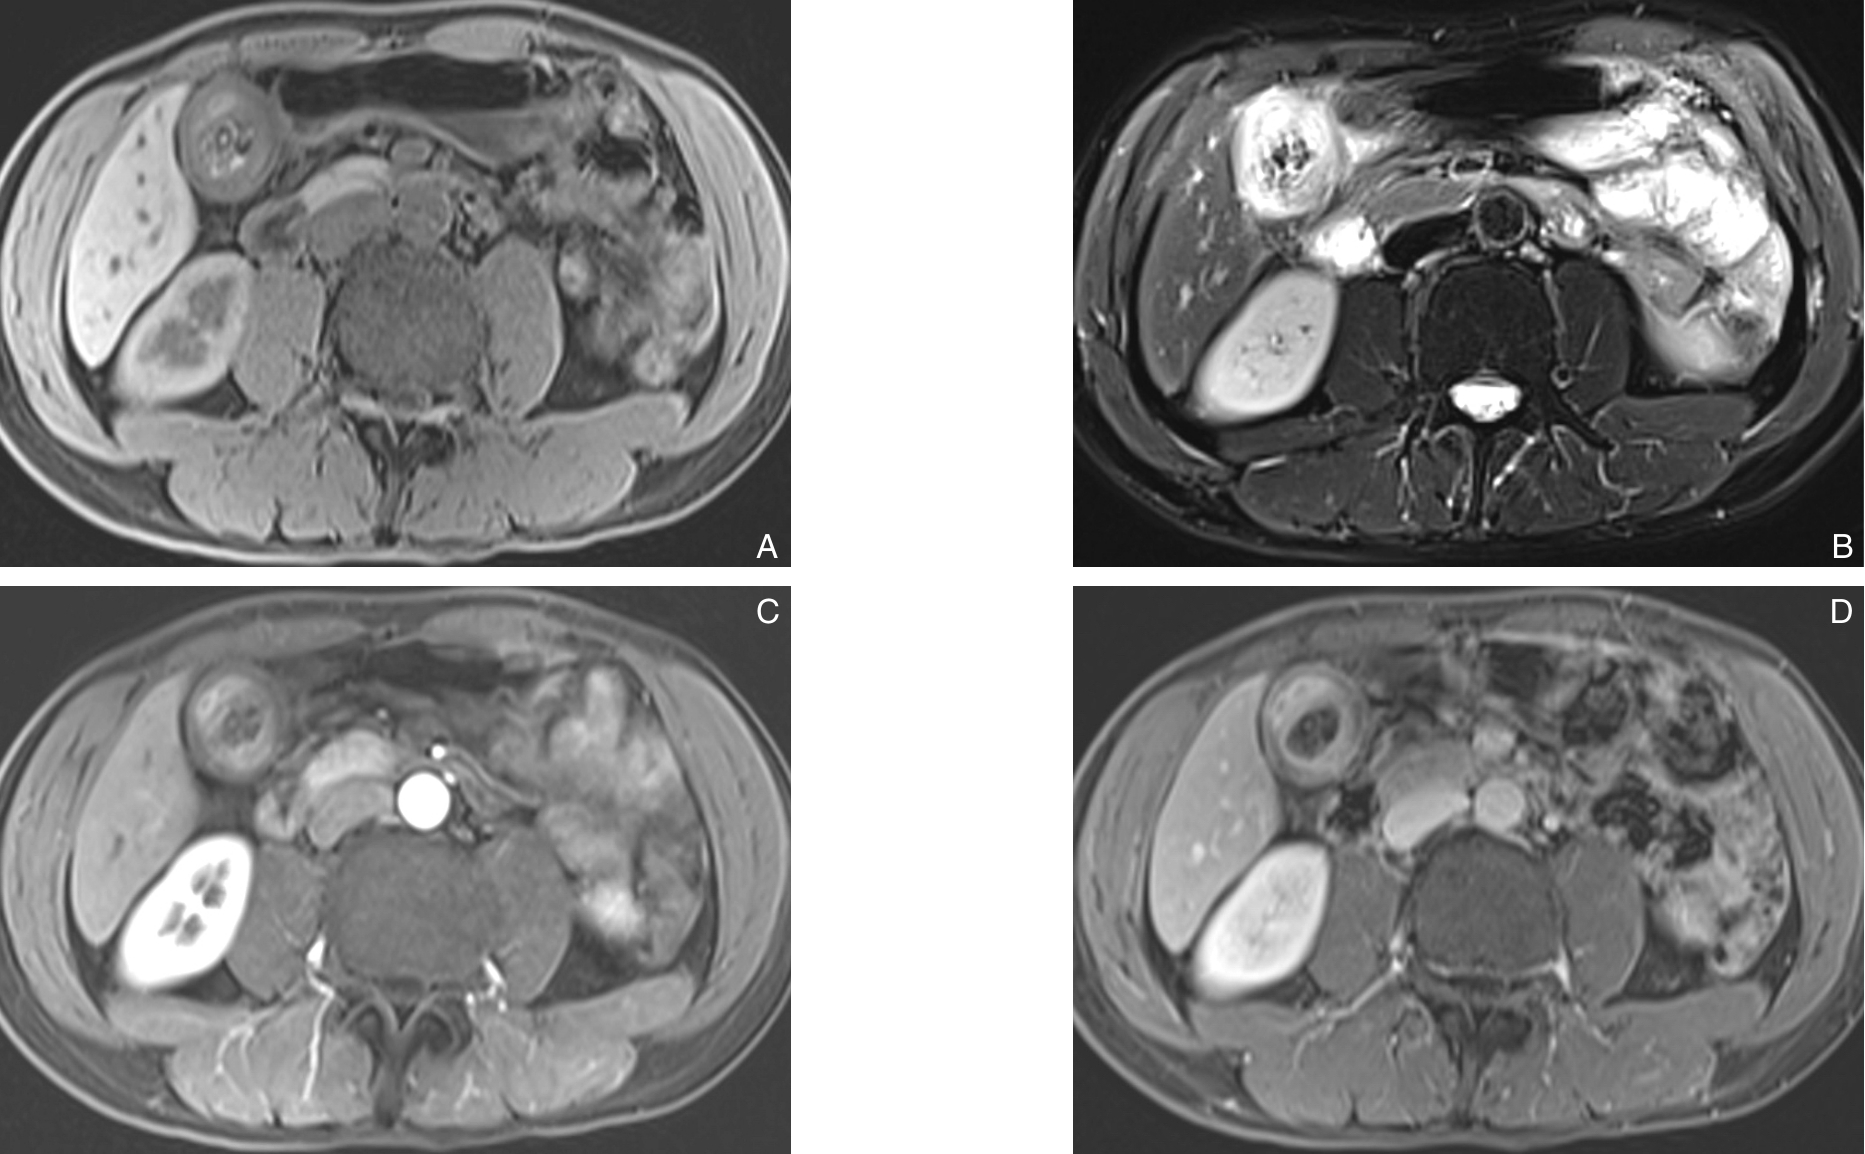

2025, 34(12):2596-2604. doi: 10.7659/j.issn.1005-6947.250360

摘要:背景与目的 Ⅱ型内漏(T2EL)是腹主动脉瘤腔内修复术(EVAR)后最常见的并发症之一,其中部分患者可进展为瘤腔持续扩张并需再次干预。明确EVAR术后进展性T2EL的危险因素并进行风险分层,有助于优化围术期管理和随访策略。本研究旨在分析EVAR术后进展性T2EL的相关危险因素及其危险阈值,并构建预测模型。方法 回顾性分析2013年3月—2024年12月在天津医科大学总医院行EVAR术后出现T2EL的腹主动脉瘤患者临床资料。依据随访期间是否达到T2EL干预指征(瘤体最大直径与基线相比增加≥10 mm),将患者分为进展组(n=21)和稳定组(n=62)。比较两组患者的临床特征、解剖条件及手术相关因素,采用多因素Logistic回归分析筛选进展性T2EL的独立危险因素,通过受试者工作特征(ROC)曲线确定危险阈值,并构建列线图预测模型,对模型进行判别度、校准度及临床实用性评价。结果 进展组患者的瘤体最大直径、肠系膜下动脉(IMA)开口直径及通畅腰动脉(LA)数量均显著高于稳定组(均P<0.05)。多因素分析显示,瘤体最大直径、IMA开口直径及通畅LA数量是EVAR术后进展性T2EL的独立危险因素(均P<0.05)。ROC曲线分析表明,瘤体最大直径≥54.30 mm、IMA开口直径≥2.82 mm及通畅LA数量≥6条时,发生进展性T2EL的风险显著增加。基于上述因素构建的列线图模型一致性指数为0.858,经Bootstrap内部验证后校正一致性指数为0.837,模型具有良好的判别能力、校准度及临床获益。结论 瘤体最大直径、IMA开口直径及通畅LA数量是EVAR术后进展性T2EL的重要危险因素。基于上述因素构建的列线图预测模型可有效评估进展性T2EL的发生风险,但仍需多中心、前瞻性研究进一步验证。